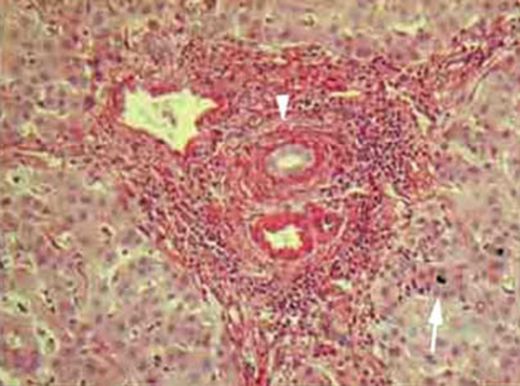

Hepatit B Tanısı Hepatit B tanısı, genellikle kan testleri ile konulur. Bu testler, Hepatit B virüsüne karşı antikorların varlığını ve virüsün yükünü belirlemek için kullanılır. Ayrıca, karaciğerin hasarını değerlendirmek amacıyla ultrason veya biyopsi gibi görüntüleme yöntemleri de kullanılabilir. Hepatit B Tedavisi Hepatit B tedavisi, enfeksiyonun türüne ve hastanın sağlık durumuna bağlı olarak değişir. Akut Hepatit B enfeksiyonu genellikle tedavi gerektirmeden kendiliğinden iyileşebilir. Ancak, kronik Hepatit B hastalarında tedavi süreci daha karmaşık olabilir. Tedavi yöntemleri arasında şunlar bulunmaktadır: